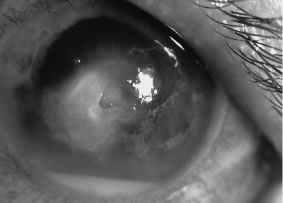

There is no distinguishing clinical sign by which to recognize the genus or species of the infectious filamentous fungus. F. solani is the most virulent organism and typically produces rapidly progressive infection characterized by epithelial and stromal ulceration, dense stromal necrosis, abundant cellular infiltrate, and edema in the adjacent stroma and hypopyon (Figs. 8 and 9). Delicate feathery components are transient. Individual hyphal fragments are rarely visualized. Infection by certain species of Aspergillus and Scedosporium (Figs. 10 and 11) resembles F. solani keratitis and progresses rapidly. Infection by less virulent organisms, such as Curvularia and Alternaria species, produces small, focal (less than 3-mm diameter) areas of nonnecrotizing stromal inflammation with delicate feathery borders (see Fig. 1 and Fig. 12). Macroscopic pigmentation may develop in keratitis caused by Alternaria, Curvularia, and other dematiaceous fungi (Fig. 13).4,11,14 The central component may progress to dense, opaque, gray-white suppuration in the deep stroma without enlargement in total area and may be accompanied by mild inflammation in the adjacent stroma. Iritis is minimal to moderate. Infection caused by other, relatively less virulent organisms resembles herpes simplex or noninfectious keratitis (Fig. 14).

Fig. 8. F. solani keratitis. Note the dense opaque central necrosis surrounded by fluffy, nonhomogeneous infiltrate.

Fig. 9. F. solani keratitis. Epithelial and stromal ulceration and necrotizing stromal keratitis.